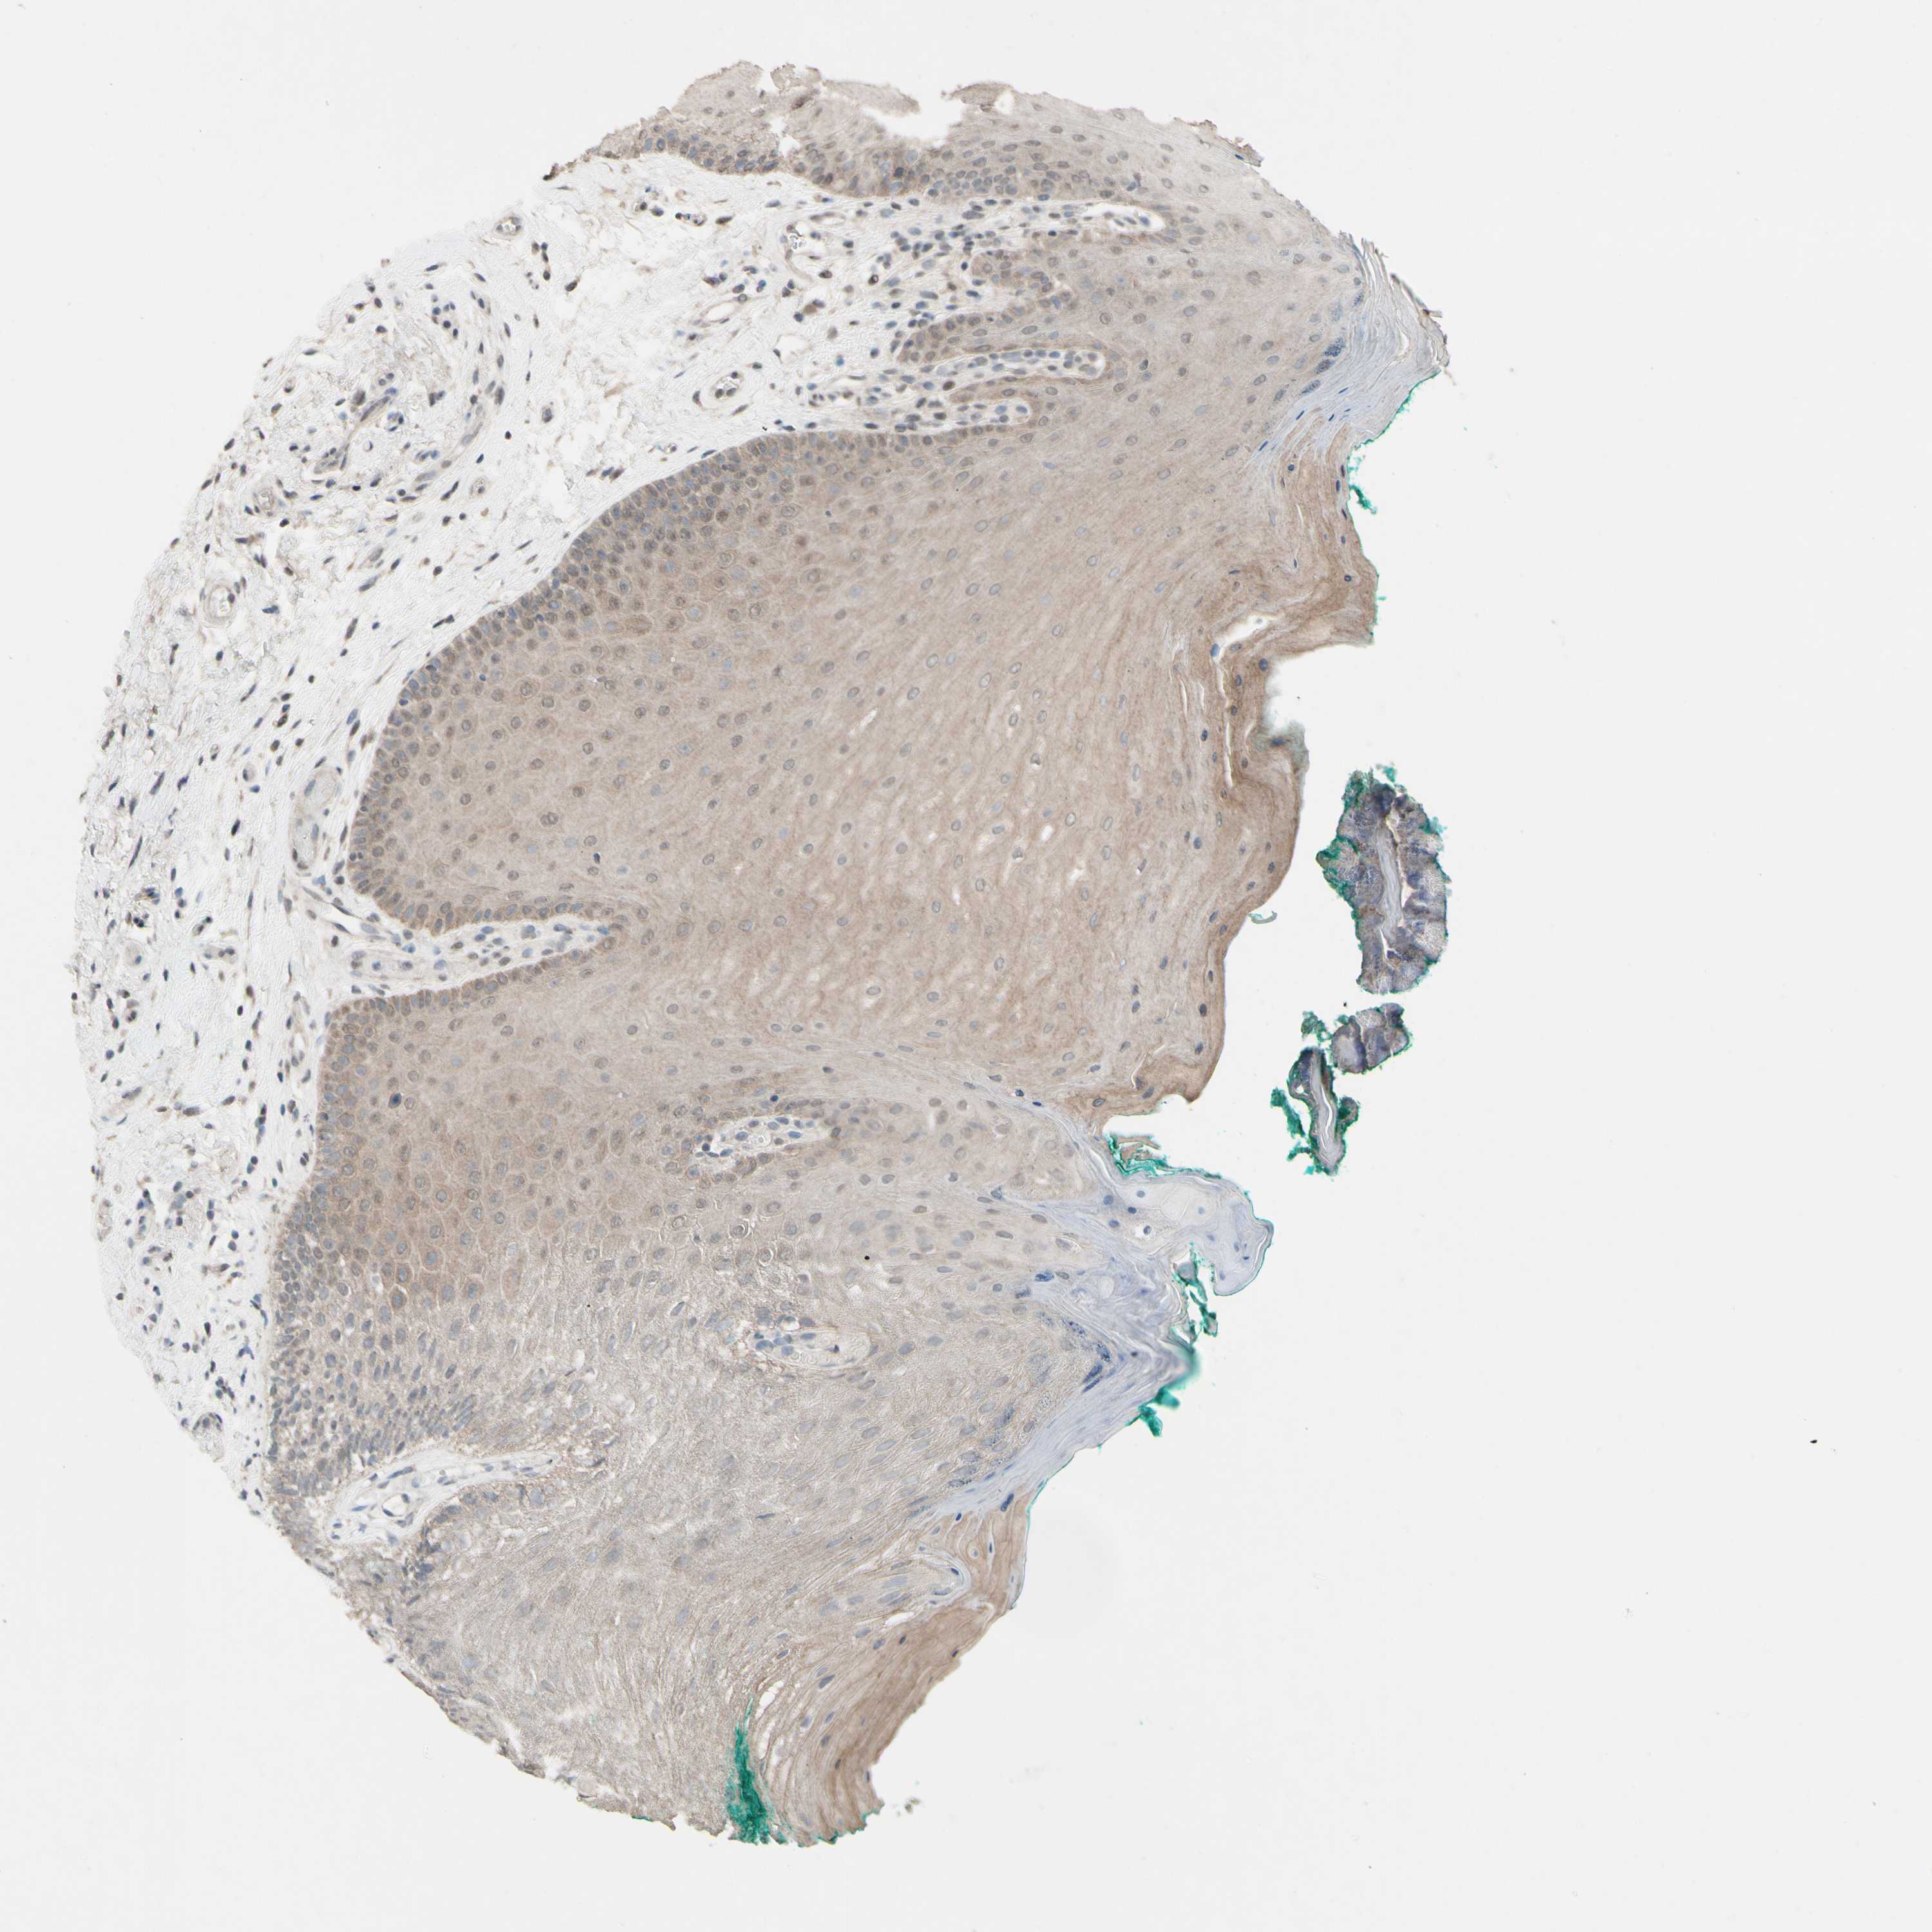

CDCP1